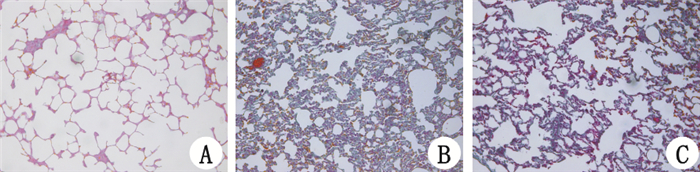

2.2.1 肺组织病理改变(HE及Masson染色)染毒 7 d : A 组肺泡间隔为单层,未见增厚,肺泡腔内未见渗出物;B 组肺泡炎性改变明显,间隔增宽,其中可见大量炎症细胞,血管扩张充血,间质水肿,肺泡腔内可见大量渗出液,甚至出血;C 组肺泡炎性渗出及出血相对 B 组为轻。14 d:A 组肺泡间隔为单层,未见增厚,肺间质无实变、纤维化改变;B 组肺泡间质水肿及渗出较7 d 时有所减轻,间隔增宽,肺间质可见呈绿色的胶原纤维增多,出现肺间质纤维化;C组肺泡间隔增宽的厚度相对B组较轻,胶原纤维较B组少,间质纤维化沉积程度相对 B 组较轻。28 d:A 组肺泡数量丰富,肺泡间隔为单层,未见增厚,肺间质无实变、纤维化改变,肺结构正常;B 组肺泡正常结构消失,间隔增厚普遍可见绿色的胶原纤维沉积,残存的肺泡腔出现过度膨胀,表现为肺泡扩张明显,肺泡间隔断裂,相邻的肺泡腔融合成较大的囊腔,肺泡结构紊乱;C 组间隔中的胶原纤维化沉积相对B组较轻,也可见肺泡融合的大囊腔,但肺泡基本结构仍可见,见图 1~6。

![]() |

| 图 3 染毒28 d各组大鼠肺组织病理改变(HE ×200) Fig 3 Pathological changes in the lung tissue of each group at 28 days after PQ administration(HE ×200) |